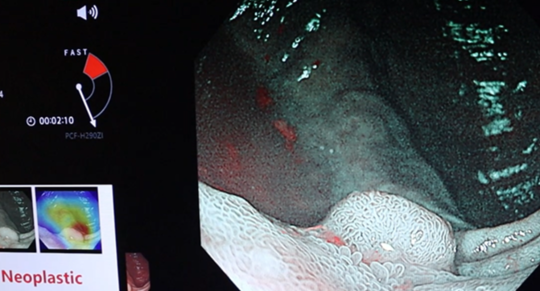

EndoBRAIN-Xによる腫瘍・非腫瘍の鑑別も

見つけた大腸病変のNBI拡大内視鏡画像をAIでも判断。経験豊富な内視鏡医が診断することはもちろんですが、AIにても解析し,瞬時にポリープの腫瘍・非腫瘍の鑑別を行っています。

③狭帯域光(NBI)にて診断

通常の白色光による診断に続き、腫瘍・非腫瘍の鑑別に優れた狭帯域光(NBI)を使用した拡大内視鏡診断を行います